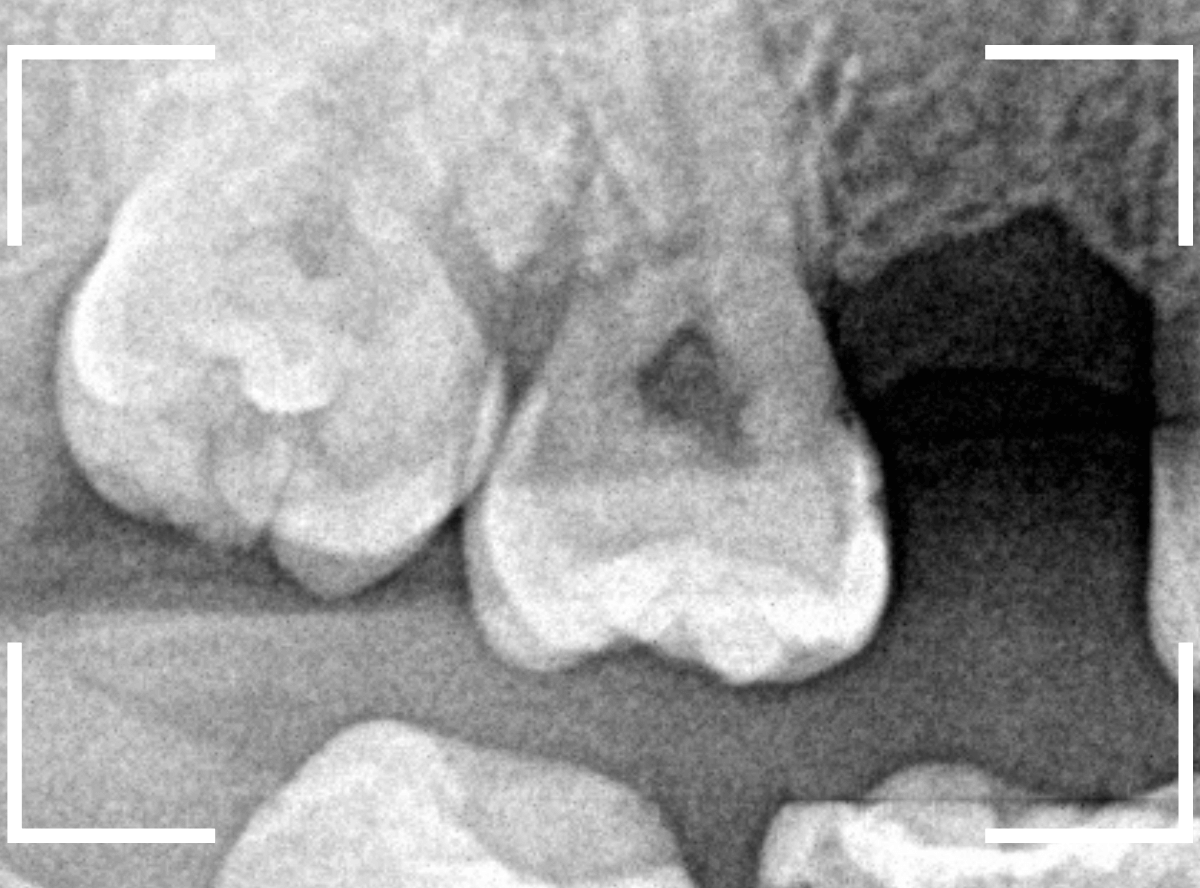

ここでは、比較的簡単なおやしらずの抜歯の例を中心にご紹介します。

このようなおやしらず、あなたはありませんか?